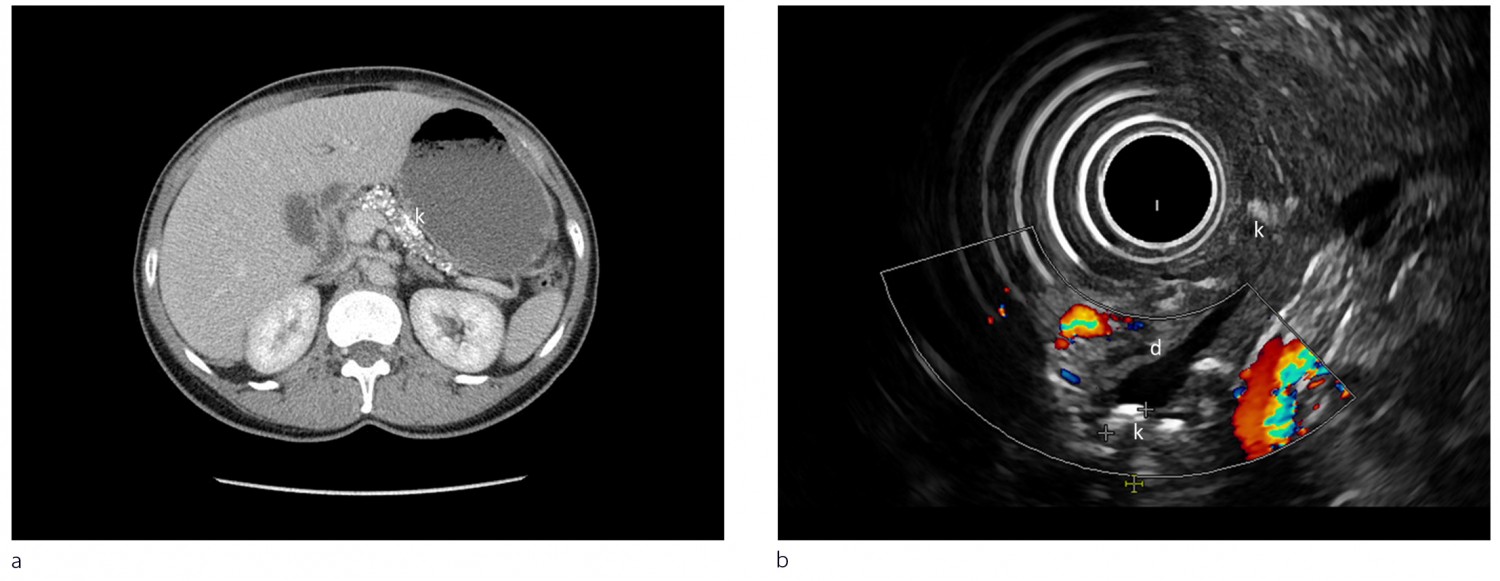

Radiologiske modaliteter som computertomografi (CT), magnetisk resonanstomografi (MR) og endoskopisk eller ekstern ultralydundersøkelse brukes til å påvise forandringer ved kronisk pankreatitt. Ved milde forandringer er endoskopisk ultralyd den mest sensitive metoden (1, 2). Fordeler og ulemper med de enkelte metoder med eksempler presenteres i figur 2 og ramme 3.

Endoskopisk ultralyd: Gir god fremstilling av gang- og vevsforandringer og er førstevalget ved tidlige kroniske pankreatittforandringer. Gir mulighet for biopsi av lesjoner i pancreas og tapping av pseudocyster